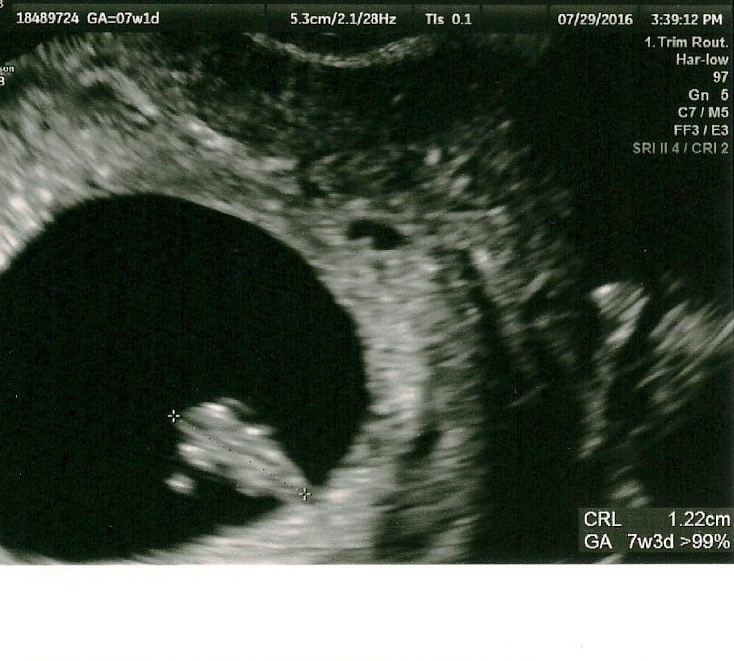

I got to see my two little ones and hear their heartbeats again this week at 7w4d. They are pretty clearly di/di. I "graduated" from the REs office and cried in the elevator leaving, it was really overwhelming. Sorry to keep posting all my ultrasound photos but staring at them is the only thing that keeps me from losing my mind with all the nausea and vomiting. And we haven't told anyone else so I have to keep telling you all!